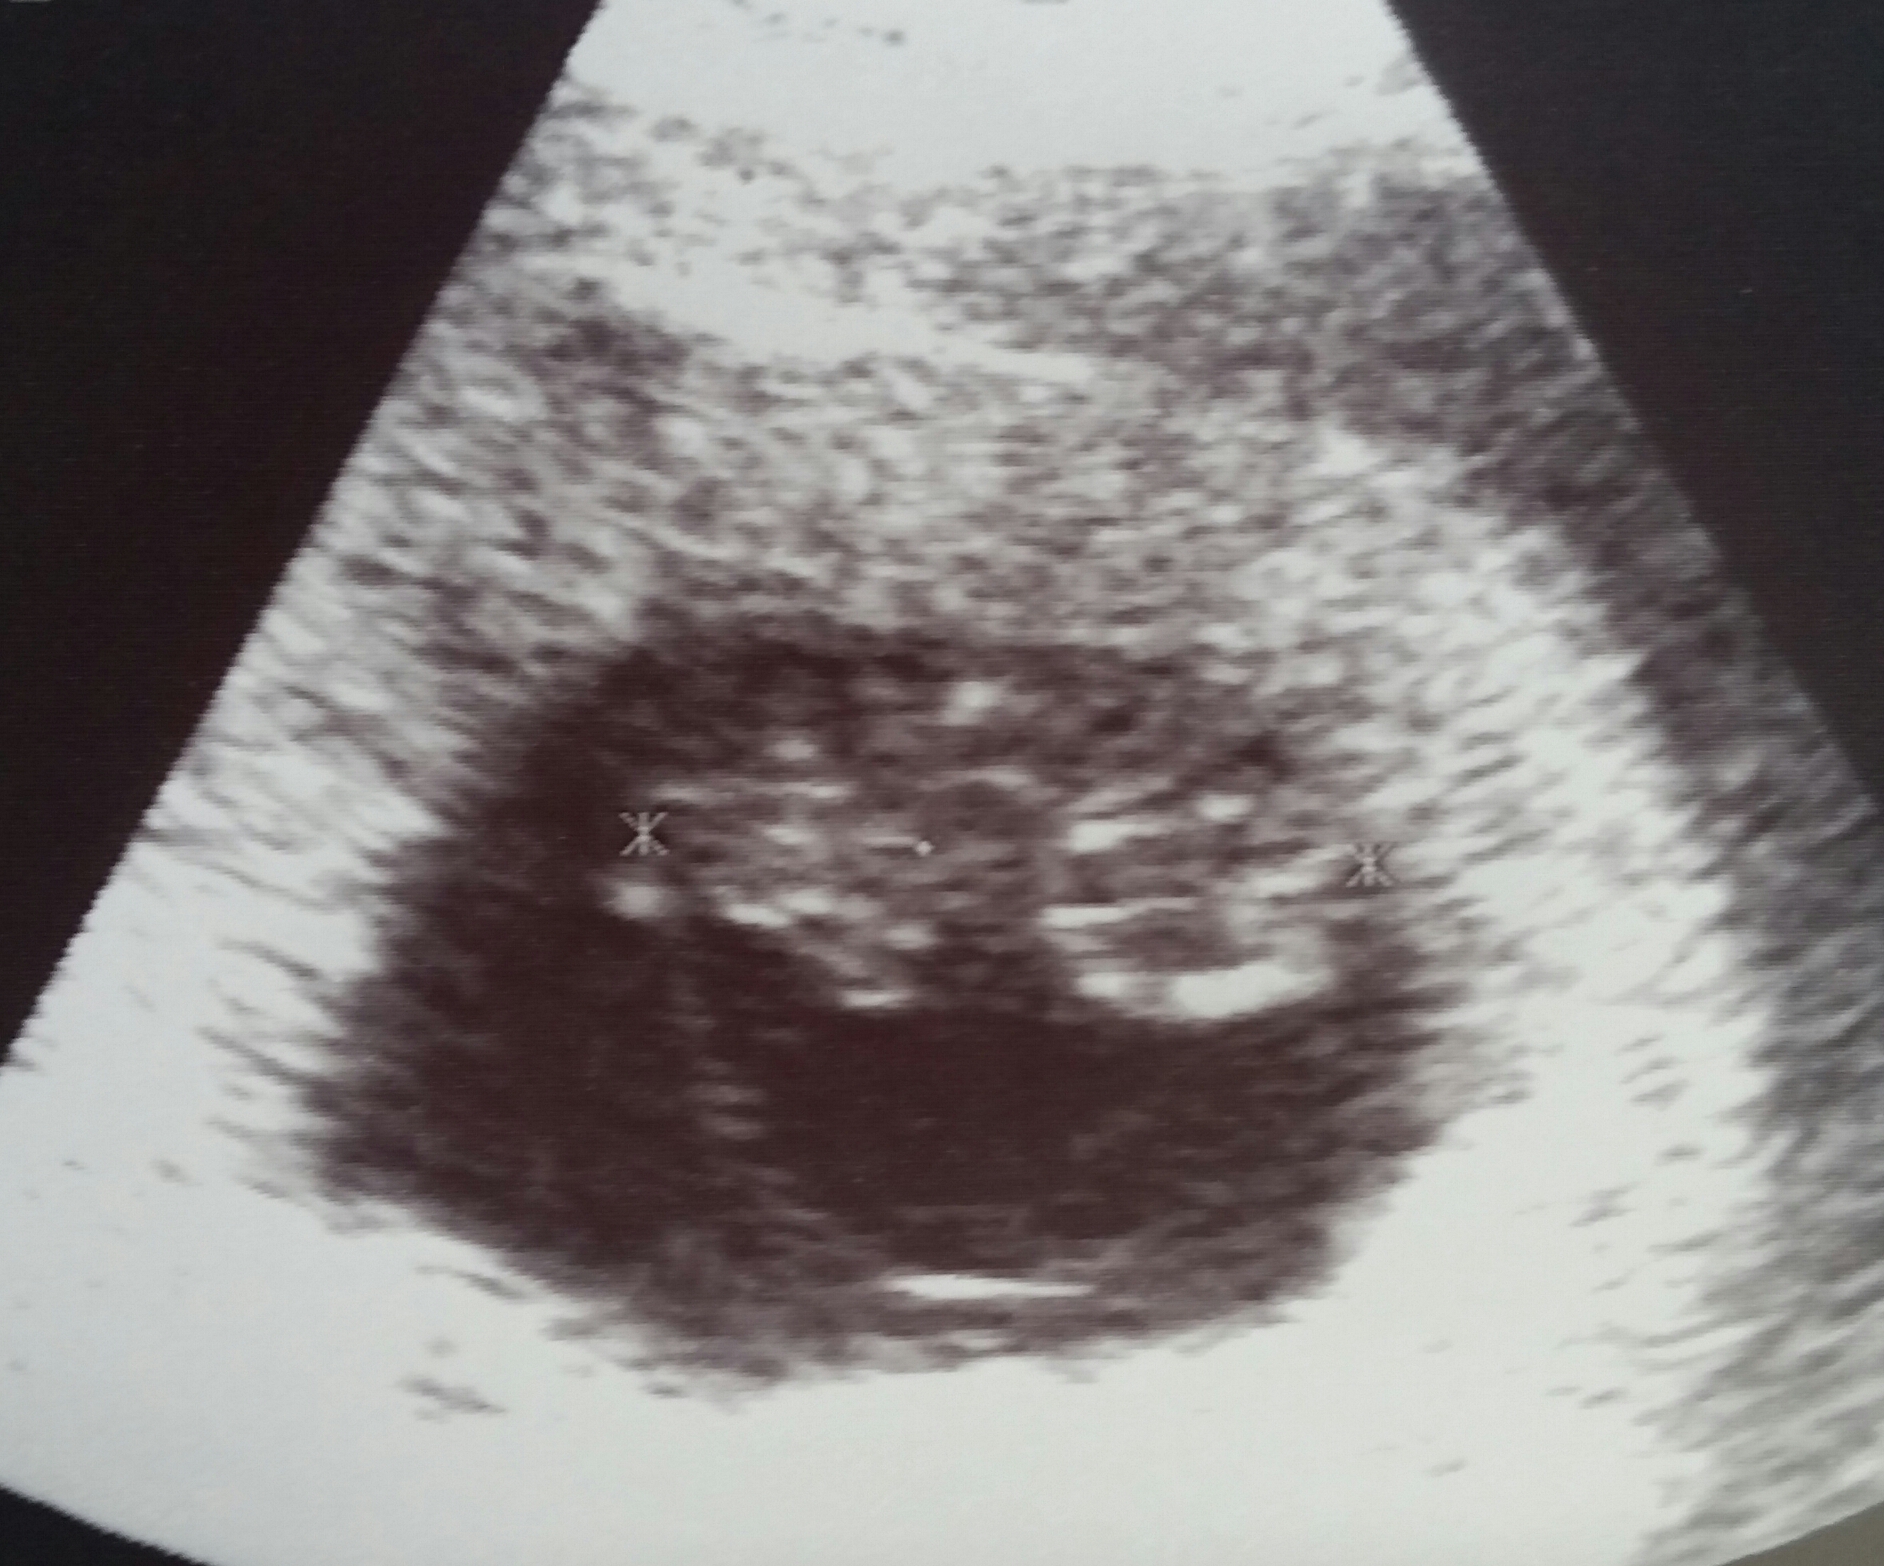

But now, after seeing everyone elses pics Im a little worried that my gestational sac is funny shaped?? My RE didnt mention anything.... should I be concerned?!